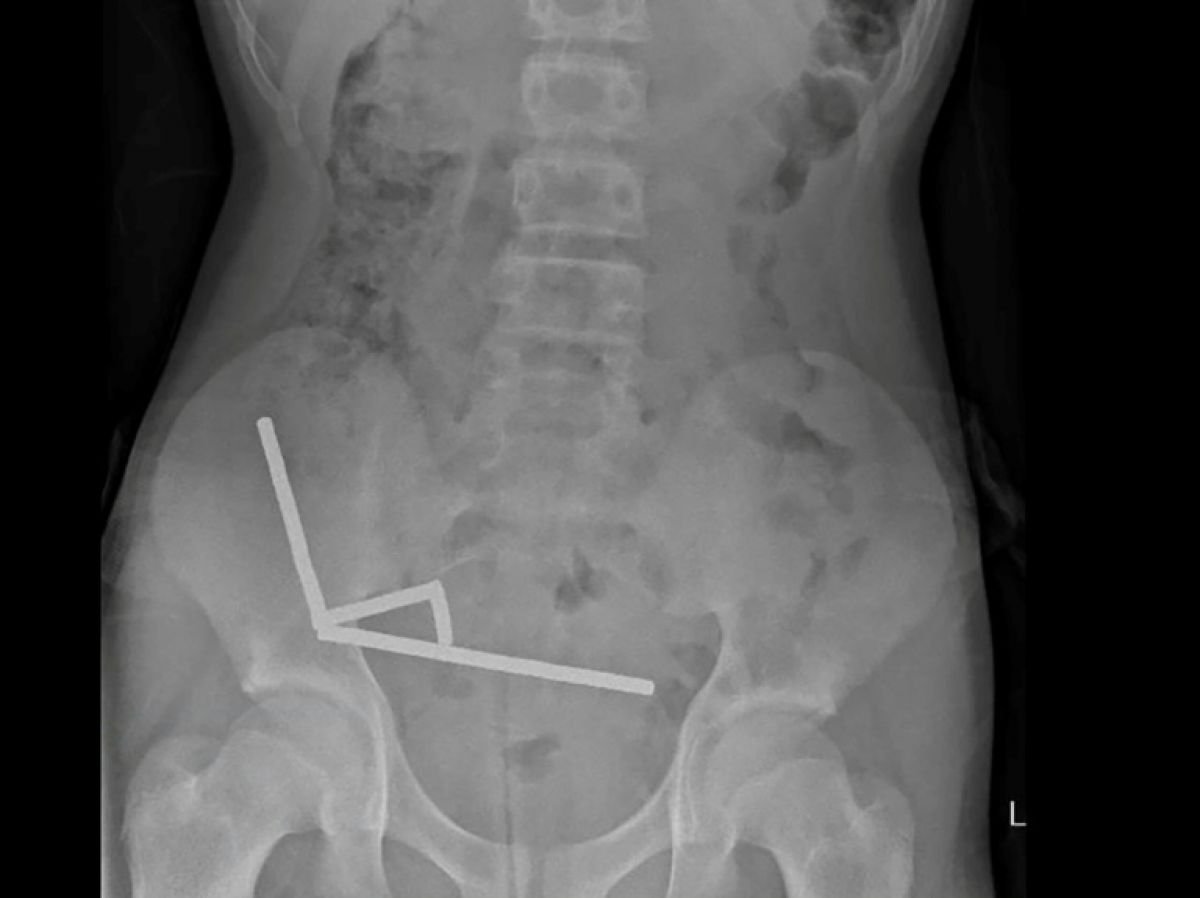

Depois de sentir dores abdominais durante quatro dias, o adolescente foi levado ao hospital em Tauranga, na Ilha Norte. “Ele admitiu ter ingerido entre 80 e 100 poderosos ímãs de neodímio, aproximadamente 5x2mm, uma semana antes”, indica relatório dos médicos do hospital deste hospital, publicado no Revista Médica da Nova Zelândia (NZMJ).

Este tipo de íman, proibido na Nova Zelândia desde janeiro de 2013, foi alegadamente adquirido na plataforma de comércio eletrónico chinesa Temu. Os médicos disseram que a pressão dos ímãs causou necrose em quatro áreas dos intestinos delgado e grosso do menino.

Ele passou por uma cirurgia para remover os ímãs e o tecido morto e conseguiu voltar para casa após oito dias internado. O artigo explica que a cirurgia após a ingestão do ímã pode levar a complicações, como obstrução intestinal, hérnia abdominal e dor crônica.